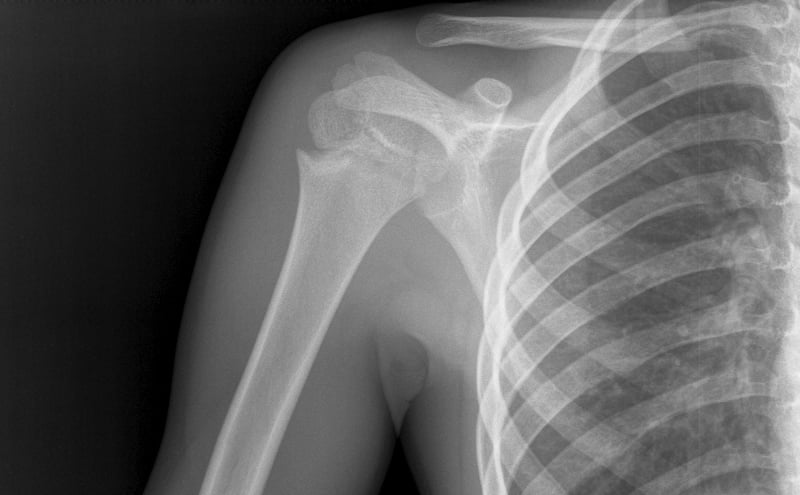

• Cervical spine injury

• Pneumothorax/Hemothorax

Cardiac tamponade